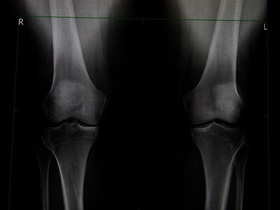

Ендопротезування колінного суглоба в Києві

Ендопротезування колінного суглоба — це заміна його пошкоджених природних частин на штучний ендопротез. Не завжди є потреба у тотальному ендопротезуванні, при якому замінюються всі суглобові компоненти. У частині випадків достатньо часткової заміни, якщо решта структур суглоба можуть надалі виконувати свої функції. Це визначається під час діагностики, рішення про вибір методу приймає лікар.